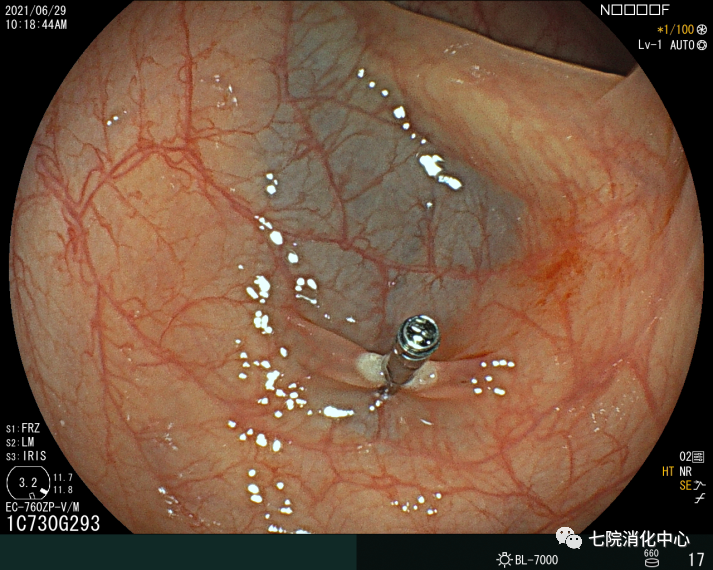

常用于切除无蒂息肉,通过注射缓冲液到黏膜下层的空间,使上皮与底层组织分开,使病变分离。包括整块切除和分次切除,目前黏膜下注射切除法是最常用的一种EMR切除法,其他EMR切除方法还有透明帽辅助EMR、注水法/水下法EMR等,EMR在实现大肠息肉的完整内窥镜切除术方面明显优于冷圈套器,但它需要黏膜下注射和电灼,因此不可避免出现延迟出血、息肉切除术后综合征和穿孔等并发症。

ESD:

ESD相对于EMR而言,可最大限度地减少肿物的残留和复发。ESD通常应用>20mm、非颗粒样侧向发育病变。ESD相对于传统的分片黏膜切除术来说是一种复发率低、可获得更好的病理标本的技术。ESD的不足是穿孔率高、过程耗时。多项研究表明,ESD穿孔率约5%。大量研究报告了ESD的临床结果,整块切除的疗效好以及大型浅表结直肠肿瘤的长期低复发率。